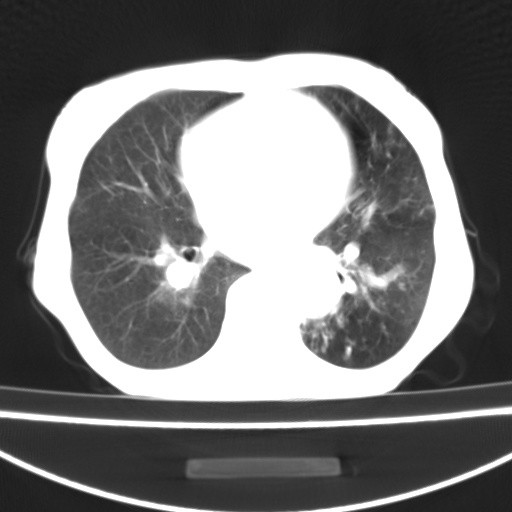

患者 女 67岁,反复咳嗽咳痰2年,加重伴喘及双下肢浮肿1月

诸大血管及f肺门血管增粗迂曲.左下肺多发薄壁空腔影.部分非也透亮度增高.薄曾扫描可区分肺气肿类型.考虑1.慢性支气管炎 2.左下肺支气管扩张 3.肺气肿 4 肺动脉高压5.是否有先心病病史

考虑1.慢性支气管炎 2.左下肺支气管扩张 3.肺气肿 4 肺动脉高压

慢支炎、肺气肿、双肺感染、左下囊状支扩。

慢支、肺气肿、肺动脉高压;左下肺囊状支扩并粘液栓形成。